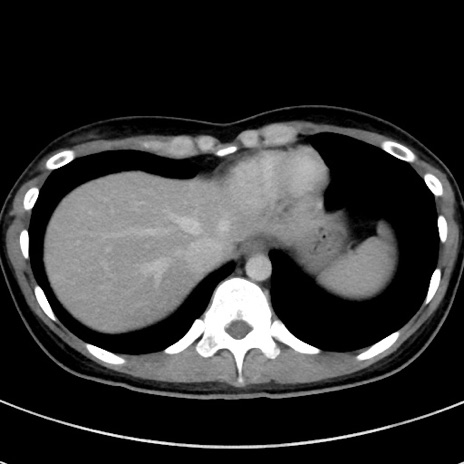

症例17(横断像)

【症例】20歳代女性

【主訴】嘔吐、下腹部痛

【現病歴】昨日夕食後に嘔吐し下腹部痛が出現。本日になっても嘔吐持続し改善しないため来院。

【身体所見】意識清明、BT 37.2℃、BP 108/67mmHg、腹部:平坦、やや硬、下腹部正中から右にかけて圧痛あり、反跳痛軽度あり、tapping pain(+)。

【データ】WBC 13600、CRP 14.94